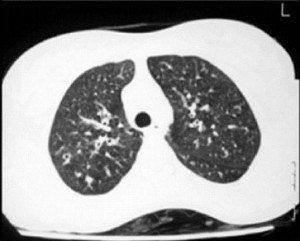

Akciğer grafisi

Tamamen normal görülebilir ya da, hilustan dışarı doğru uzanan radyolusent çizgiler (tram lines) veya kalın paralel çizgiler (tooth paste lines) veya kümelenmiş kistler görülebilir. Bazen bu kistlerin içinde hava-sıvı seviyeleri görülebilir. Peribronşial kalınlaşma, atelektazi veya konsolidasyon gibi nonspesifik bulgulare da olabilir.

Rutin laboratuvar testleri tanıda çok az yardımcıdır. Ağır, yaygın hastalığı olanlarda kanda lokositoz, anemi olabilir. Klinik özellikler ve hikaye düşündürüyorsa, altta yatan hastalığa yönelik testler yapılır. Ter testi, immunglobulinlerin istenmesi gibi. ‘‘Bronkografi’’ tanıda altın standarttır. Ancak günümüzde bronkografi kadar detaylı görümtü sağlayan ve noninvaziv olan yüksek rezolusyonlu kompütörize tomografi bronkografinin yerini almıştır.